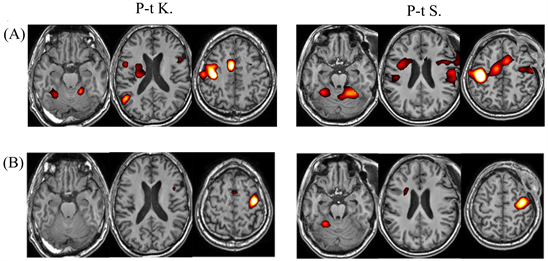

The inter-group comparison of fMRI reactions (patients and healthy subjects) revealed the greatest differences in moving the dominant right hand (Figure 3(A)). A diffuse component of fMRI responses was present in patients, while

Figure 3. Comparison of fMRI responses during (A) right-hand movement and (B) left-hand movement between a group of TBI patients and healthy subjects (p(unc) < 0.001, with cluster correction for multiple comparisons р(FWE-corr) < 0.01, patient group > group of healthy subjects).

responses were more local in healthy subjects. Moreover, the subcortical structures and various nonspecific cortical areas of the contralateral hemisphere were significantly more involved in responses in TBI patients, which is not common for the motor response of healthy subjects. In general, the left-hand movement caused no significant differences in fMRI responses between the groups (Figure 3(B)). However, there were slight differences in the occipital cortex and subcortical structures. Furthermore, the fMRI activation volume was slightly higher in the patient group.

Individual fMRI responses in the TBI group presented high inter-individual variation, but all the patients had the diffuse form of brain response, in contrast to the healthy group with a more expressive response to right-hand movement s (Figure 4(A)). The execution of this task in patients involved a larger number of cerebral structures compared to the norm; this effect manifested itself in both hemispheres (Figure 4(B)). Less distinctive features were observed in fMRI responses to left-hand movement in patients with TBI compared to healthy subjects (Figure 4(A), Figure 4(B)).

Figure 4. Examples of individual fMRI responses during right-hand movement (A) and left-hand movement (B) in P-t K. and P-t S.